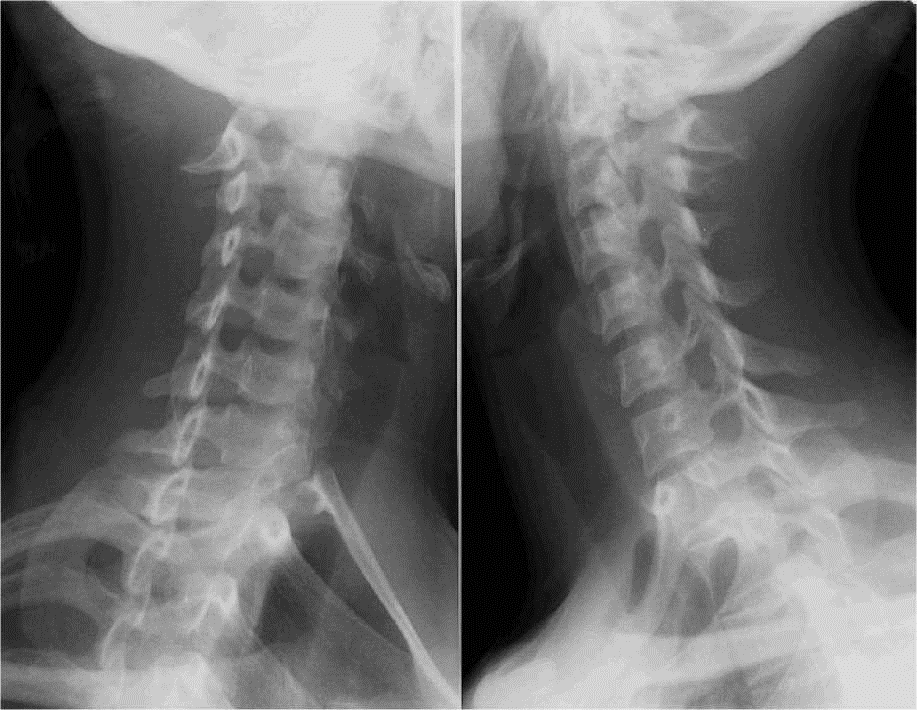

DROIT GAUCHE

FLEXION/EXTENSION

– – 1 cliché de profil en flexion – – 1 cliché de profil en extension

FLEXION

EXTENSION